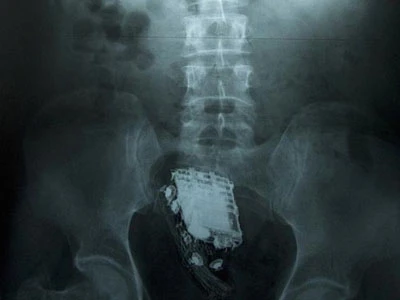

Gã tù nhân 58 tuổi bị ban quản lý nhà tù Welikada (Kotte, Sri Lanka) đưa đến bệnh viện cấp kỳ. Kết quả chụp X-quang phơi bày chiếc điện thoại đang ngự trong bụng ông ta và các bác sĩ phải giải phẫu lấy ra.

Chiếc điện thoại trú ngụ trong ruột tù nhân. Ảnh: Daily Mail